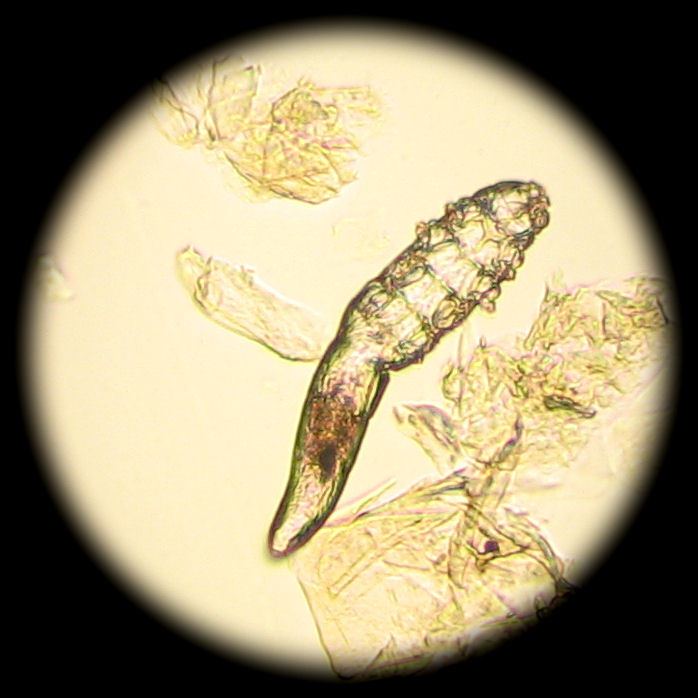

Так, например, выяснилось, что взрослый клещ достигает максимального размера до 0,4 мм. У него полупрозрачное вытянутое туловище и 8 лапок. Тело покрыто мелкими чешуйками, которые позволяют им цепляться за волосяной фолликул. Кроме того, у этого существа есть ротовой аппарат, с помощью которого ему удается поедать скапливающиеся в волосяных сумках частички сальных желез, клетки кожи и гормоны.

Анализ на клеща демодекс делается просто и безболезненно. Специалист берет соскоб кожи лица или волосяного покрова (брови, ресницы) и отправляет его на исследование в лабораторию. Далее проводится его изучение под микроскопом. Именно так можно увидеть полупрозрачных паразитов и результаты их жизнедеятельности.

Исключительно по внешним признакам определить наличие клеща практически невозможно. Поэтому пораженные участки следует изучить под микроскопом.

Затем врач-дерматолог проводит соскоб с кожи лица в нескольких местах. Соскоб рассматривается под микроскопом, анализ не занимает более 10 минут. Диагноз ставят при обнаружении на коже более 5 клещей на 1 см². Если клещей меньше, то ставят диагноз носительства.

Начиная с г. D.folliculorum не видны невооруженным глазом, вам нужно будет обратиться к врачу, чтобы поставить точный диагноз. Чтобы диагностировать этих клещей, ваш врач соскоблит небольшой образец фолликулярной ткани и масла с вашего лица. Биопсия кожи, показанная под микроскопом, может определить наличие этих клещей на лице.

Клещи слишком малы, чтобы их можно было увидеть невооруженным глазом, поэтому врач обычно делает биопсию кожи. Для этого нужно взять образец кожи и изучить его под микроскопом.